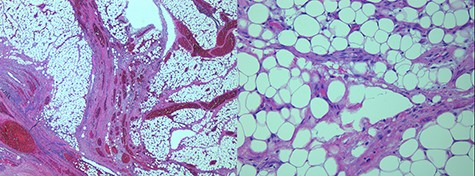

Microscopic images of the omental lipoblastoma taken through a 2.5X (left) and 20X (right) objectives on hematoxylin and eosin-stained histological sections.

A 4-year-old girl presented to our Paediatric Emergency Department for persistent lower quadrants abdominal pain following a blunt abdominal trauma, which occurred few hours before while playing with other children in a public park. Remarkably, the abdominal pain was described as a constant pressure associated with urge to urinate. The patient’s past medical history was uneventful. Physical examination was unremarkable except for a tenderness of lower abdomen. Blood tests showed a neutrophilic leucocytosis (white blood cell (cells/mm3): 14 810; neutrophils (%): 71) and elevated levels of C-reactive protein (122 mg/L). An abdominal ultrasound (US) scan was performed, demonstrating a hyperechoic and inhomogeneous solid mass (10 x 4 x 8 cm), located cranially to the bladder with no vascular signal at color doppler. Remarkably, the left ovary was not visualized at the US scans. Tumor markers on blood test revealed high level of cancer antigen125 (220.9 IU/ml), while levels of beta human chorionic gonadotropin, alphafeto-protein and carcinoembryonic antigen were within normal limits. Due to the laboratory findings, broad-spectrum antibiotic therapy was started. Suspecting an ovarian mass and/or adnexal torsion, the patient underwent abdominal exploration through a Pfannenstiel incision. Both ovaries appeared in normal status, and a solid well-encapsulated mass originating from the great omentum twisted around his vascular peduncle was found (Fig. 1). Histologic examination of the mass revealed a large encapsulated lipoblastoma arising from the greater omentum which was totally excised (Figs 2 and 3), and cytogenetic analysis did not show any chromosomal rearrangements. The postoperative course was unremarkable. The patient was discharged home on postoperative day 5. Sonographic follow-up and levels of cancer antigen125 repeated at 3 months postoperatively were normal.

Lipoblastomas are rare benign tumors of childhood. They are more common in males, with a peak incidence below 3 years of age. Lipoblastomas most commonly occur at the limbs followed by abdomen, head and neck [7, 8]. Occasionally, they can arise as an abdominal mass from the retroperitoneum involving the mesentery or the omentum. When arising in the abdomen, they are usually larger and can cause symptoms of compression or leading to intussusception [7]. Histologically, lipoblastoma is a well-defined entity and differential diagnosis includes lipoma, myxoid liposarcoma and differentiated liposarcoma. To date, only one case of omental lipoblastoma with no signs of torsion has been described [8]. Therefore, to our knowledge, this is the first case in the paediatric literature about an abdominal lipoblastoma arising from the greater omentum and moreover leading to its torsion.